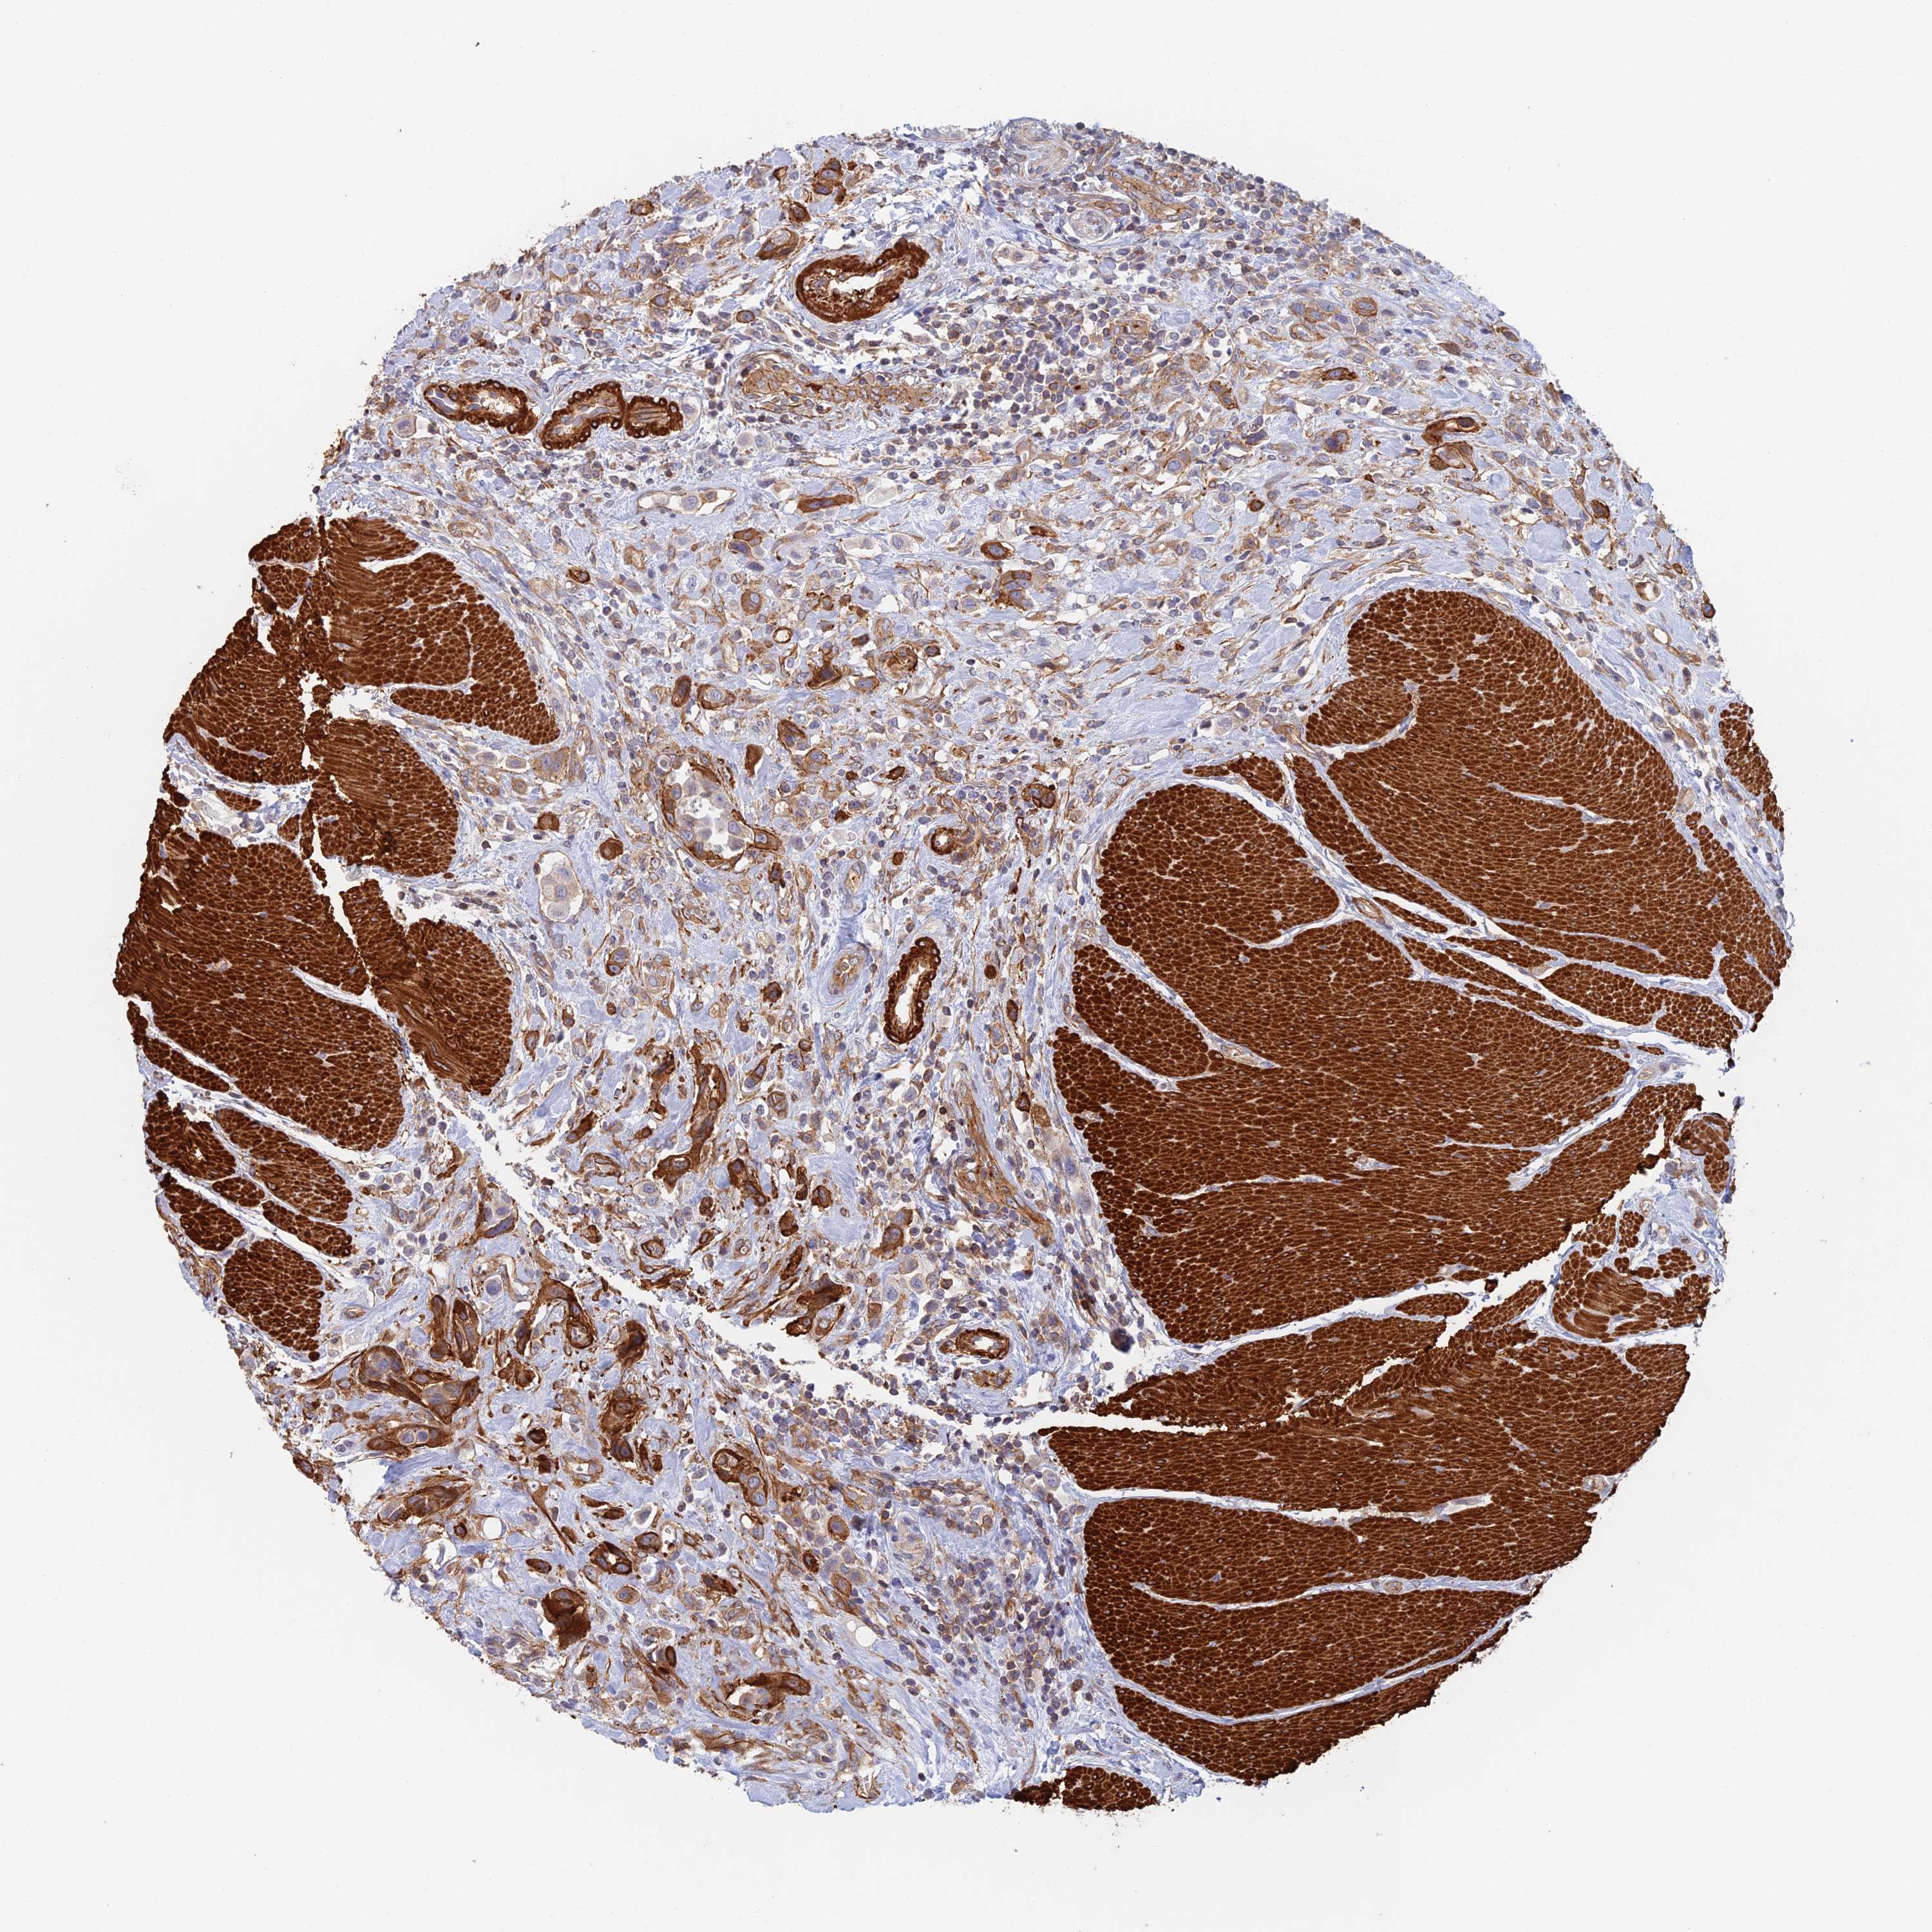

UROTHELIAL CANCER - Protein expressioni

A mouse-over function shows sample information and annotation data. Click on an image to view it in a full screen mode. Samples can be filtered based on level of antibody staining by selecting one or several of the following categories: high, medium, low and not detected. The assay and annotation is described here.

Note that samples used for immunohistochemistry by the Human Protein Atlas do not correspond to samples in the TCGA dataset.

Antibody stainingi

Antibody staining in the annotated cell types in the current human tissue is reported as not detected, low, medium, or high, based on conventional immunohistochemistry profiling in selected tissues. This score is based on the combination of the staining intensity and fraction of stained cells.

Each image is clickable and will lead to virtual microscopy that enables deeper exploration of all samples and also displays staining intensity scores, fraction scores and subcellular localization as well as patient and tissue information for each sample.

Antibody CAB025747

Antibody CAB044670

Staining

High

Medium

Low

Not detected

Intensity

Strong

Moderate

Weak

Negative

Quantity

>75%

75%-25%

<25%

None

Location

Nuclear

Cytoplasmic/membranous

Cytoplasmic/membranous,nuclear

Urothelial carcinoma, Low grade

Urothelial carcinoma, High grade